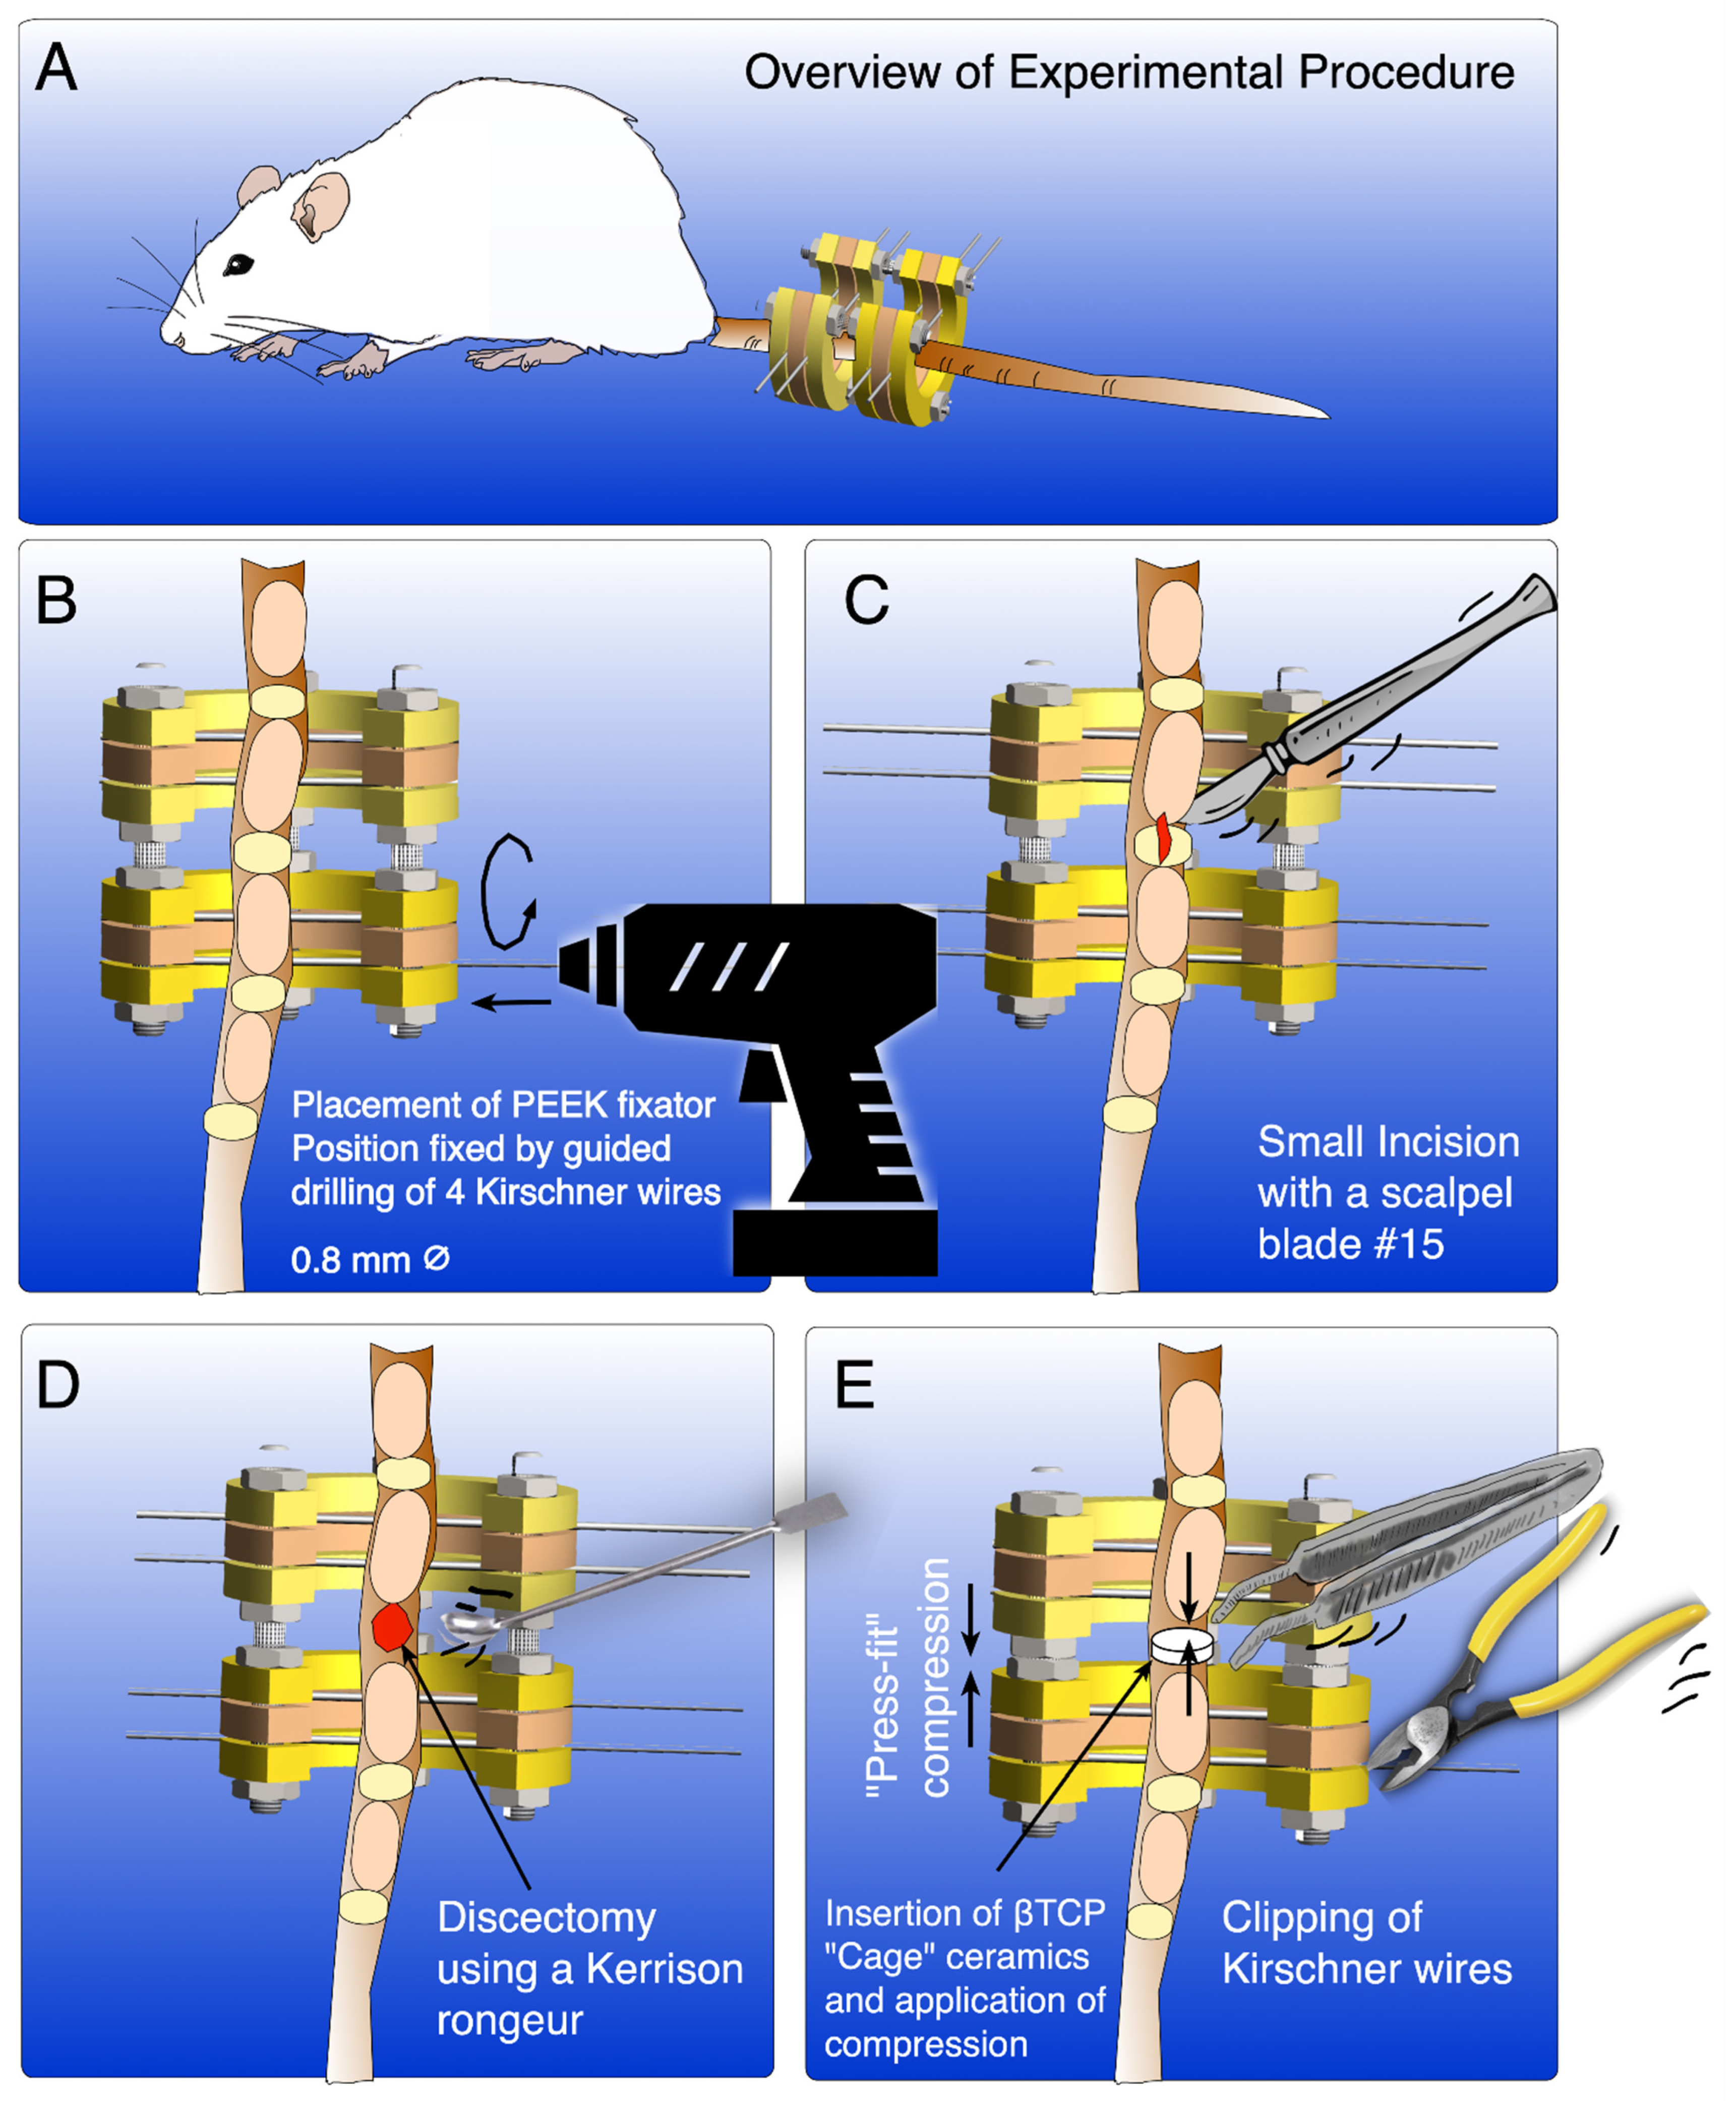

Establishment of a Novel Method for Spinal Discectomy Surgery in Elderly Rats in an In Vivo Spinal Fusion Model

2. Experimental Design

3.4. Surgical Procedure

-

- CRITICAL STEP Insert the k-wires in a slightly posterolateral direction to avoid damaging the vessels running laterally to the vertebrae.

-

- CRITICAL STEP Wound closure should be performed in a two-step process with subcutaneous closure using 4.0 Vycril and cutaneous closure with 5.0 Ethilone to ensure complete wound closure and prevent animal wound biting and wound infection.